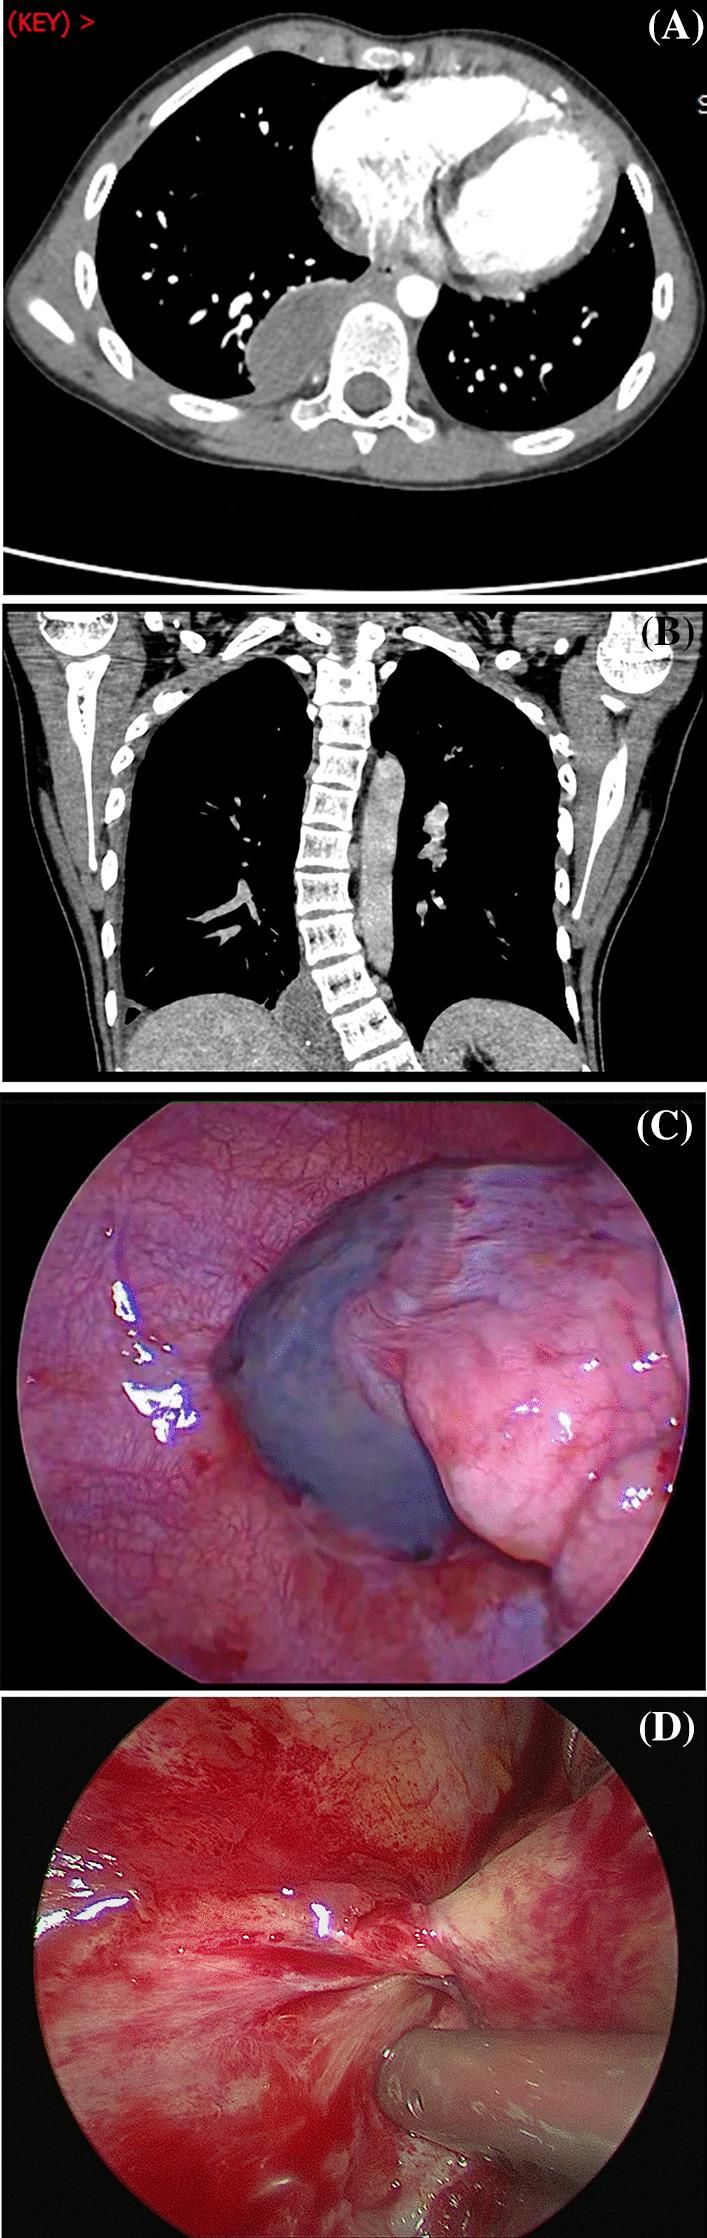

There were 6 children (3 males and 3 females), aged 3-12 years old. The main clinical symptoms of the children were abdominal and chest pain (3 cases), abdominal pain (1 case), chest pain (1 case), and vomiting and abdominal distension (1 case). Two cases were accompanied by fever. Preoperative ultrasound revealed a well-bordered mass with soft-tissue density, accompanied by pleural effusion. On contrast-enhanced computed tomography scans, the mass showed no obvious enhancement. A blood supply was only present in 1 case, and there was no feeding artery shown in the other 5 cases. Extralobar pulmonary sequestration with haemorrhagic infarction was pathologically confirmed. On postoperative days 2-6, the children were discharged uneventfully. There were no complications during the median follow-up of 4 months.

Torsed extralobar pulmonary sequestration usually occurs in childhood or adolescence, with abdominal and/or chest pain as the primary symptoms. Imaging examination shows a well-defined soft-tissue mass without enhancement. The feeding vessel is not clearly displayed in the mass, and extralobar pulmonary sequestration is accompanied by varying amounts of pleural effusion. Video-assisted thoracoscopic surgical resection is associated with excellent prognosis.